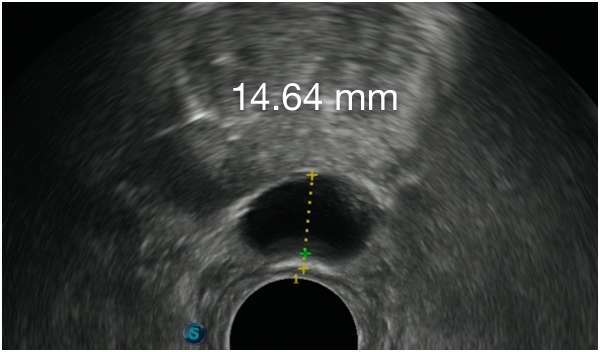

First Barrigel Cases - Consecutive Patients (Same Day)

TRUS images courtesy of Daniel R. Welchons, MD

Urologist; New York, United States